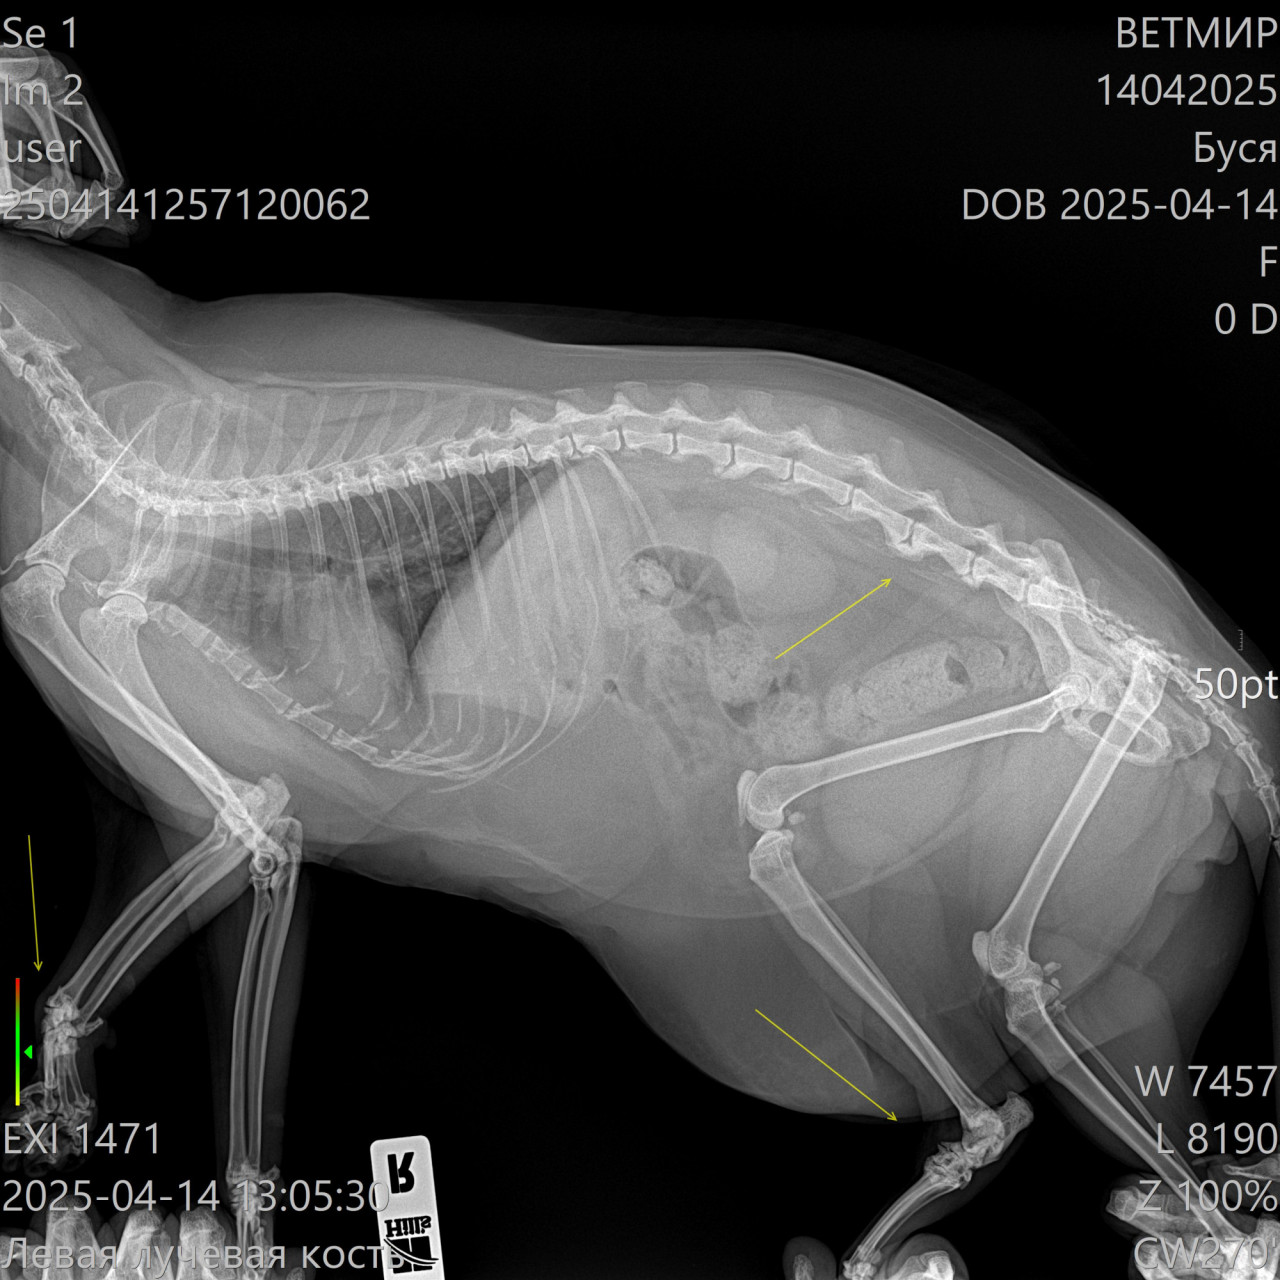

Здравствуйте. По рентгеновским снимкам у кота визуализируются дегенеративные изменения в области задних конечностей и возможные признаки остеоартроза или дисплазии тазобедренных суставов. Также может быть травматическое повреждение или врождённая деформация. Хромота в таком возрасте (12 лет) часто связана с возрастными изменениями в суставах. Необходима консультация ветеринарного ортопеда, возможно  курс противовоспалительной терапии, хондропротекторы и контроль массы тела.

Здравствуйте. На снимках отмечается нарушение конфигурации суставов и вероятные признаки хронического воспалительного процесса. Возможна артропатия или последствия перенесённой травмы. Рекомендую сдать биохимию крови (в том числе СРБ, кальций, фосфор), провести УЗИ мягких тканей конечностей и обсудить с врачом возможность обезболивания и поддерживающей терапии. В тяжёлых случаях может потребоваться МРТ и даже хирургическое вмешательство.